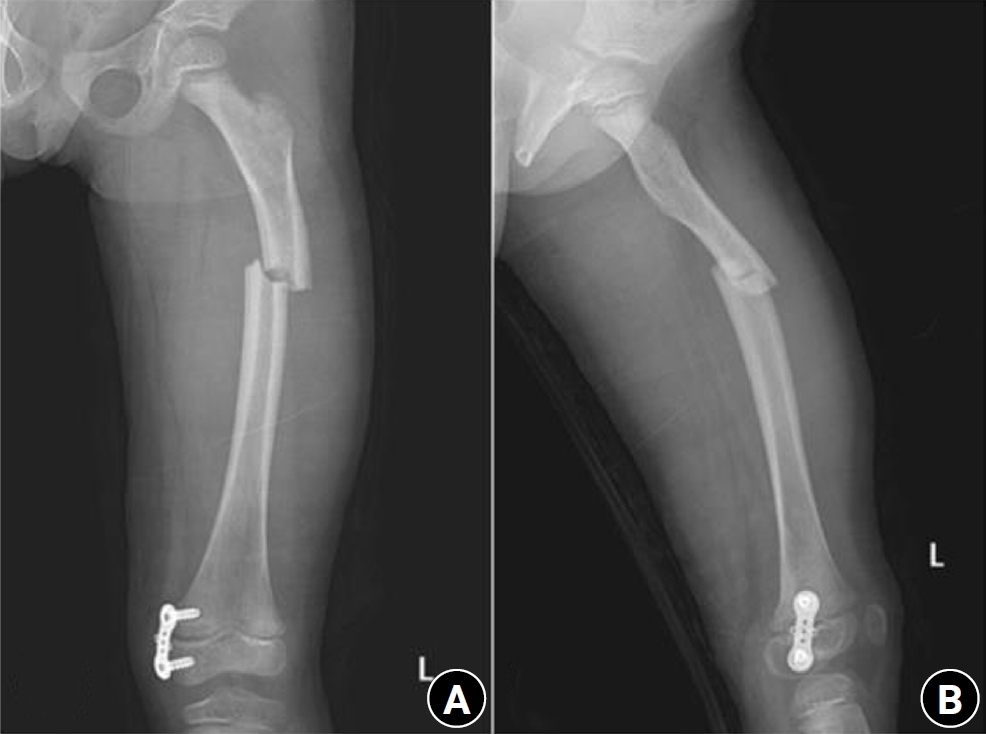

Previous studies have extensively examined the association between femoral insufficiency fractures and prolonged bisphosphonate therapy. However, alternative etiologies remain insufficiently characterized. This study aimed to analyze non-pharmacologic factors associated with femoral insufficiency fractures, with particular emphasis on paradoxical cortical hypertrophy and altered biomechanical load distribution. We reviewed three cases of femoral insufficiency fracture that were surgically treated at our institution between January 2018 and January 2022. None of the patients had a history of bisphosphonate use. Clinical histories—including underlying comorbidities, prior surgical procedures, and radiographic findings—were evaluated. Serial radiographs obtained before and after fracture occurrence were analyzed to characterize fracture morphology and associated cortical changes. Case 1 involved a patient with post-traumatic hip synostosis; case 2 involved a patient with osteogenesis imperfecta; and case 3 involved a patient who had previously undergone intramedullary nailing for an intertrochanteric fracture. Lateral femoral bowing and cortical hypertrophy preceded fracture development in two cases, whereas focal cortical hypertrophy at the distal locking screw site was observed in the third case. No history of bisphosphonate therapy was identified in any patient. Fractures developed at sites characterized by increased cortical remodeling and abnormal load concentration. Femoral insufficiency fractures can occur in the absence of bisphosphonate therapy. Paradoxical cortical hypertrophy and altered biomechanical force distribution appear to be important contributing factors. Level of evidence: IV.